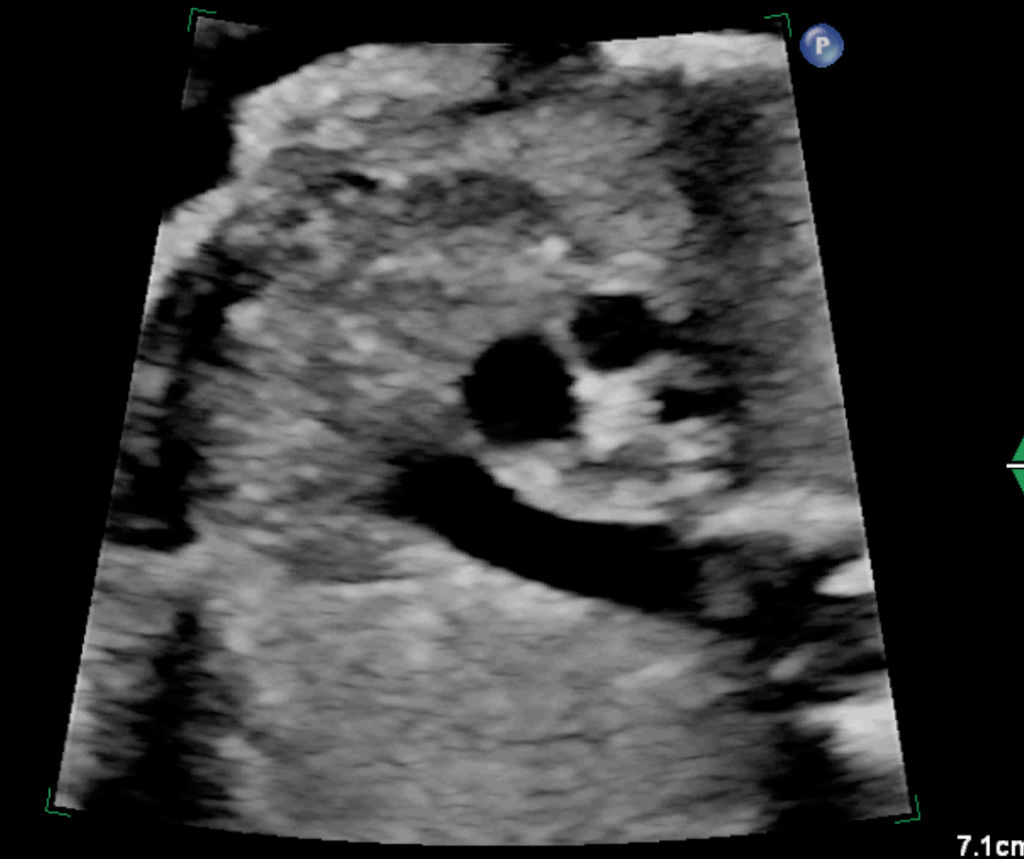

Image: Case of Fetal ToF with Right Aortic Arch with a significantly small pulmonary artery and a small Thymus. Dipicting high-risk features for the likelihood of the post-natal duct dependency and association with 22q11 deletion.